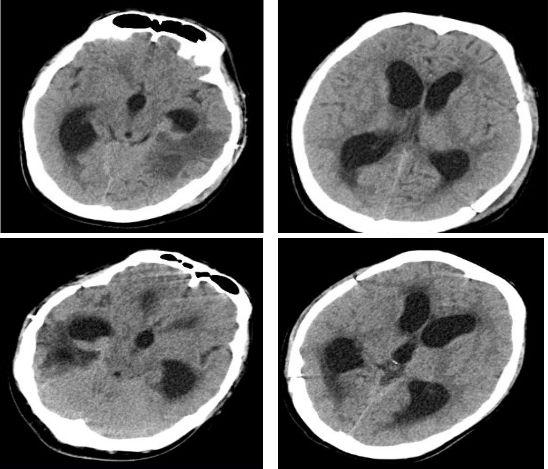

入院后头颅MRI增强显示:右侧海马占位伴出血,胶质瘤考虑(图1)。MRS:右侧海马病变部位NAA峰明显降低,Cho明显升高,Cho与NAA的比值明显加大。右侧海马病变以肿瘤可能性大。ASL灌注提示右侧海马占位明显高灌注(图2)。

图1.患者术前头颅MRI增强:右侧海马占位伴出血,胶质瘤考虑。